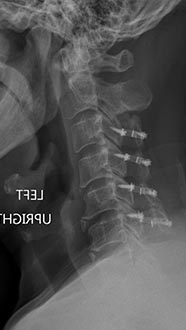

Postoperative xrays after C5-6 anterior cervical disc replacement. Complete resolution of arm pain and full painless range of motion of his neck.